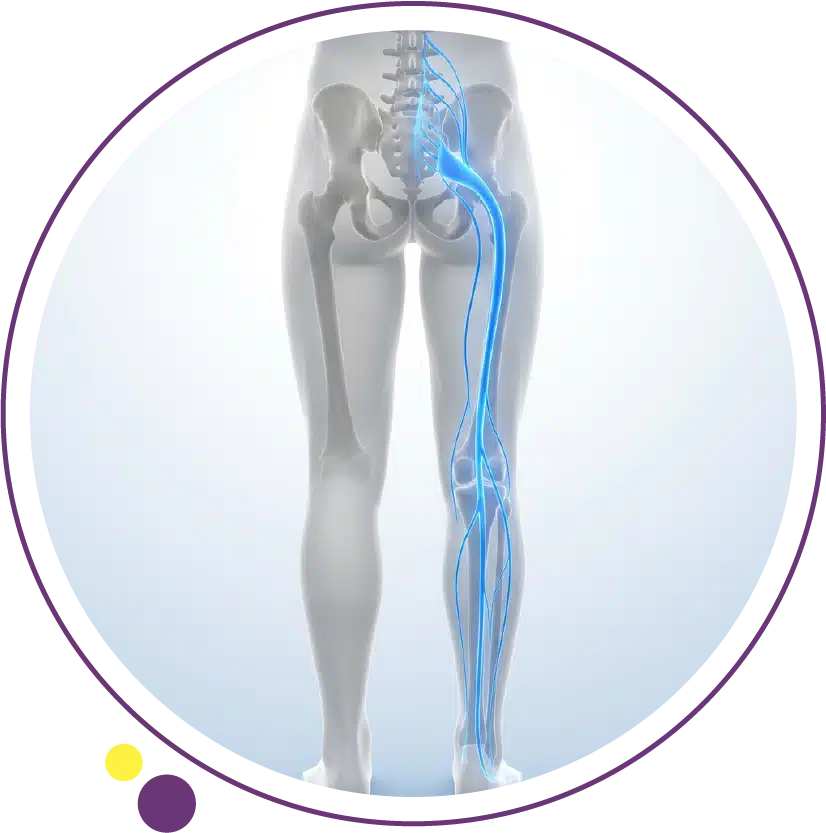

Sciatica symptoms usually happen when a nerve root in the lower back becomes irritated or compressed, causing pain and other nerve-related symptoms that travel into the buttock, leg, and sometimes the foot. Sciatica is not a diagnosis by itself. It is a symptom pattern, often linked to lumbar radiculopathy, which commonly happens when a disc problem or bony narrowing affects the nerve roots that contribute to the sciatic nerve.

Sciatica refers to pain that travels along the path of the sciatic nerve, usually from the low back into the buttock and down the back of the thigh and calf. The pain may extend below the knee and into the foot. It often happens on one side and may feel more prominent in the leg than in the lower back.

The symptoms happen because an irritated or compressed nerve root becomes inflamed and starts sending abnormal pain and sensation signals. That is why sciatica is often described as nerve pain rather than ordinary muscle pain. It may coexist with low back pain, but the leg symptoms are often what patients notice most.

Sciatica most often happens when a herniated disc or bony overgrowth puts pressure on lumbar nerve roots upstream from the sciatic nerve. Other causes can include spinal narrowing and other structural changes around the nerve roots. The result is inflammation, pain, and sometimes numbness or weakness in the affected leg.

This is why sciatica is often grouped under lumbar radiculopathy. The lower back nerve root is the problem site, but the symptoms are felt farther down along the nerve pathway. That is also why the location of symptoms can vary from one patient to another depending on which nerve root is involved.